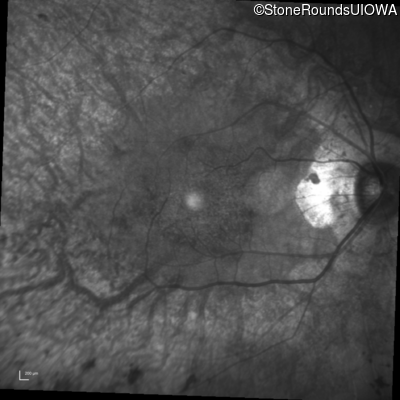

Infrared Fundus Photograph - Left - 20/20 -2

Exemplar